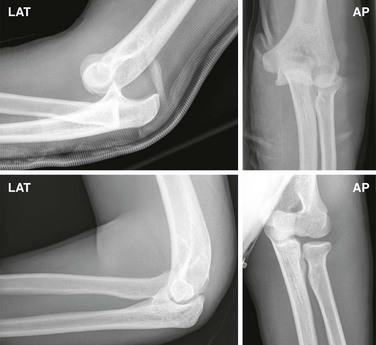

Radiologic Examination

Two radiographic views, an AP and a true lateral, should be obtained (Fig. 49-24). The diagnosis is obvious with proper radiographs. A careful search for fractures of the distal end of the humerus, radial head, and coronoid process must be undertaken since they commonly occur in this injury.75 In children younger than 14 years, the fracture is usually a medial epicondyle separation because the epiphyseal plate gives way before the medial collateral ligament of the elbow. Postreduction radiographs are also necessary to confirm reduction and disclose any associated fractures.78

Figure 49-25 Posterior elbow dislocation reduction methods.